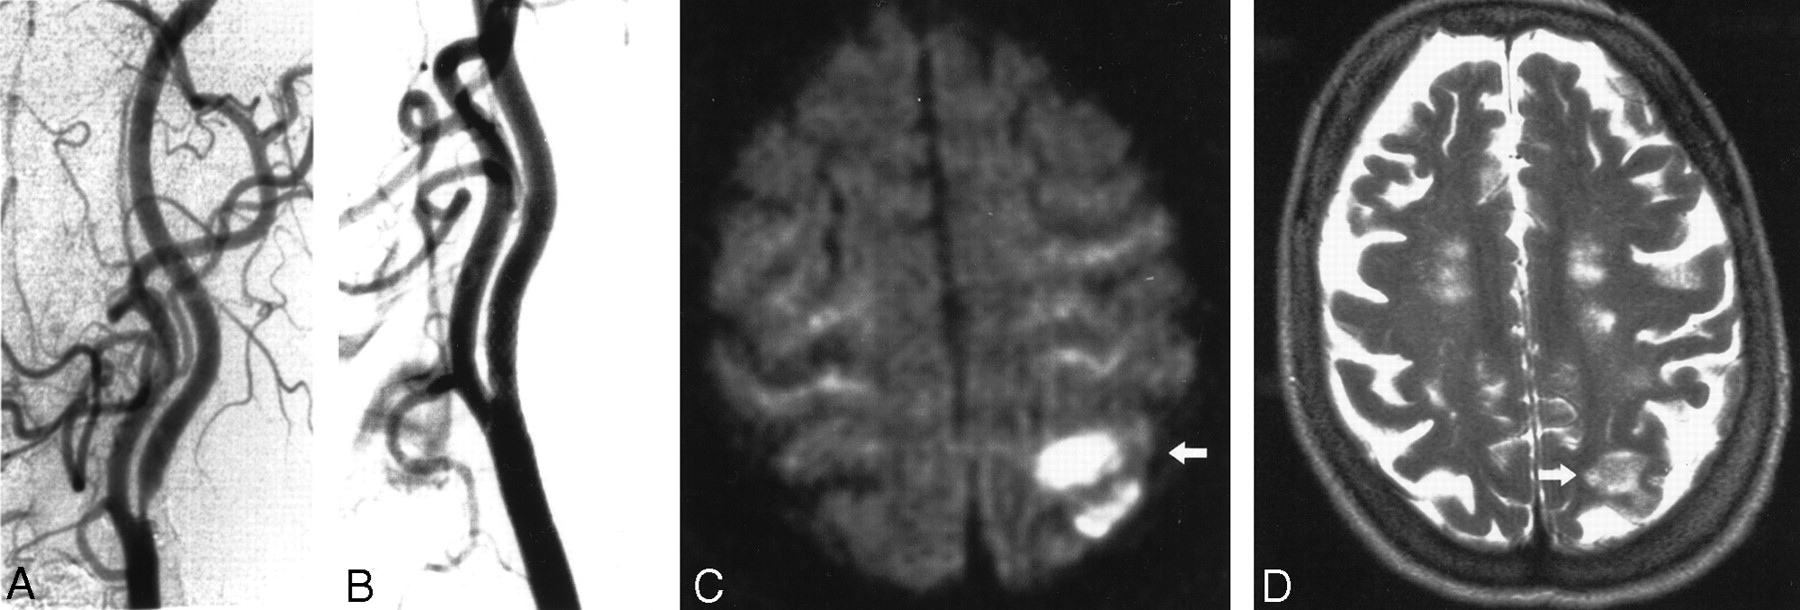

Images obtained in a 86-year-old man with a symptomatic stenosis of the carotid artery.

A, Left anterior oblique angiogram (transbrachial approach) shows an 87% stenosis of the left ICA.

B, Left anterior oblique angiogram shows the result after stent implantation.

C, Postprocedural axial diffusion-weighted MR image (6000/103/1) shows six new ipsilateral lesions (5–10 mm) in the cortical territory of the ACA (arrow).

Images obtained in a 73-year-old woman with a symptomatic stenosis of the carotid artery.

A, Left anterior oblique angiogram shows an 85% stenosis of the left ICA.

C, Postprocedural axial diffusion-weighted MR image (6000/103/1) shows eight new ipsilateral lesions (15–20 mm) in the cortical territory of the MCA (arrow).

D, Postprocedural axial T2-weighted MR image (5700/119/1) obtained at a corresponding level shows a new area of hyperintensity (arrow) that was not present in C.